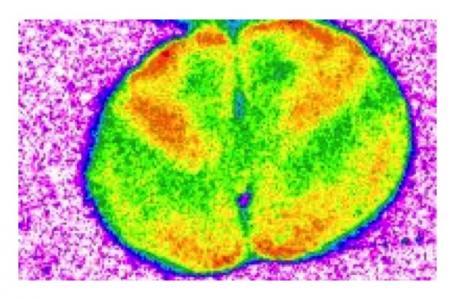

- l'imagerie cérébrale montre également que le médicament altère la fonction de zones cérébrales clés impliquées dans l'apprentissage et la mémoire ;

- de plus, l'exposition à long terme au médicament nuit à la capacité de ces zones cérébrales impliquées dans l'apprentissage et la mémoire à communiquer entre elles (cf visuel).